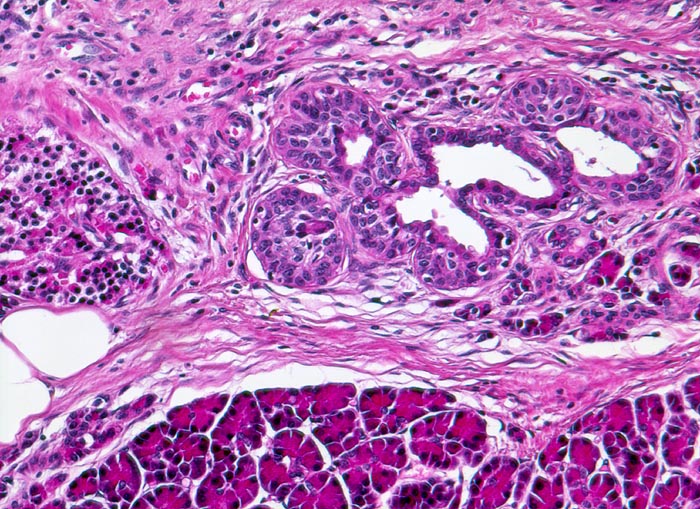

PathoPic – image database / PathoPic ID 4769 - Chronisch-sklerosierende Pankreatitis

Chronisch-sklerosierende Pankreatitis

Links im Bild eine Pankreasinsel. Daneben Inselzellen in Assoziation mit einem Gang. Ausbildung eines duktulo-insulären Komplexes = Nesidioblastose.

Alkoholiker mit rezidivierten akuten Pankreatitisschüben. Chronische Diarrhoe.

Die Nesidioblastose ist normal bei Säuglingen nachweisbar. Bei einer neonatalen Hypoglykämie sind die duktuloinsulären Komplexe deutlich vermehrt. Selten kann man die Nesidioblastose bei Erwachsenen mit hyperinsulinämischer Hypoglykämie nachweisen. Sie kann auch vorkommen beim Zollinger Ellison Syndrom, bei einer Mucoviszidose, bei endokrinen Neoplasien oder wie im vorliegenden Fall bei einer chronischen Pankreatitis.